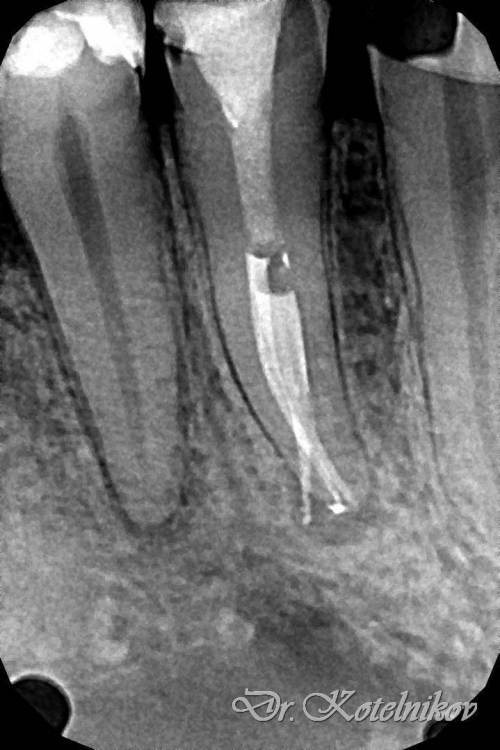

Ico Опубликовано 29 апреля, 2022 Автор Поделиться Опубликовано 29 апреля, 2022 Необратимый пульпит 47,я редко такой изгиб язычного видел. Префлеринг S1-S2(21 мм),скаут 8-10,патфаилы. Нитифлекс на 25к финиш 25.04 профаил.Мартенсита на то время не было.Паковка волна с эйчем. 5 Ссылка на комментарий